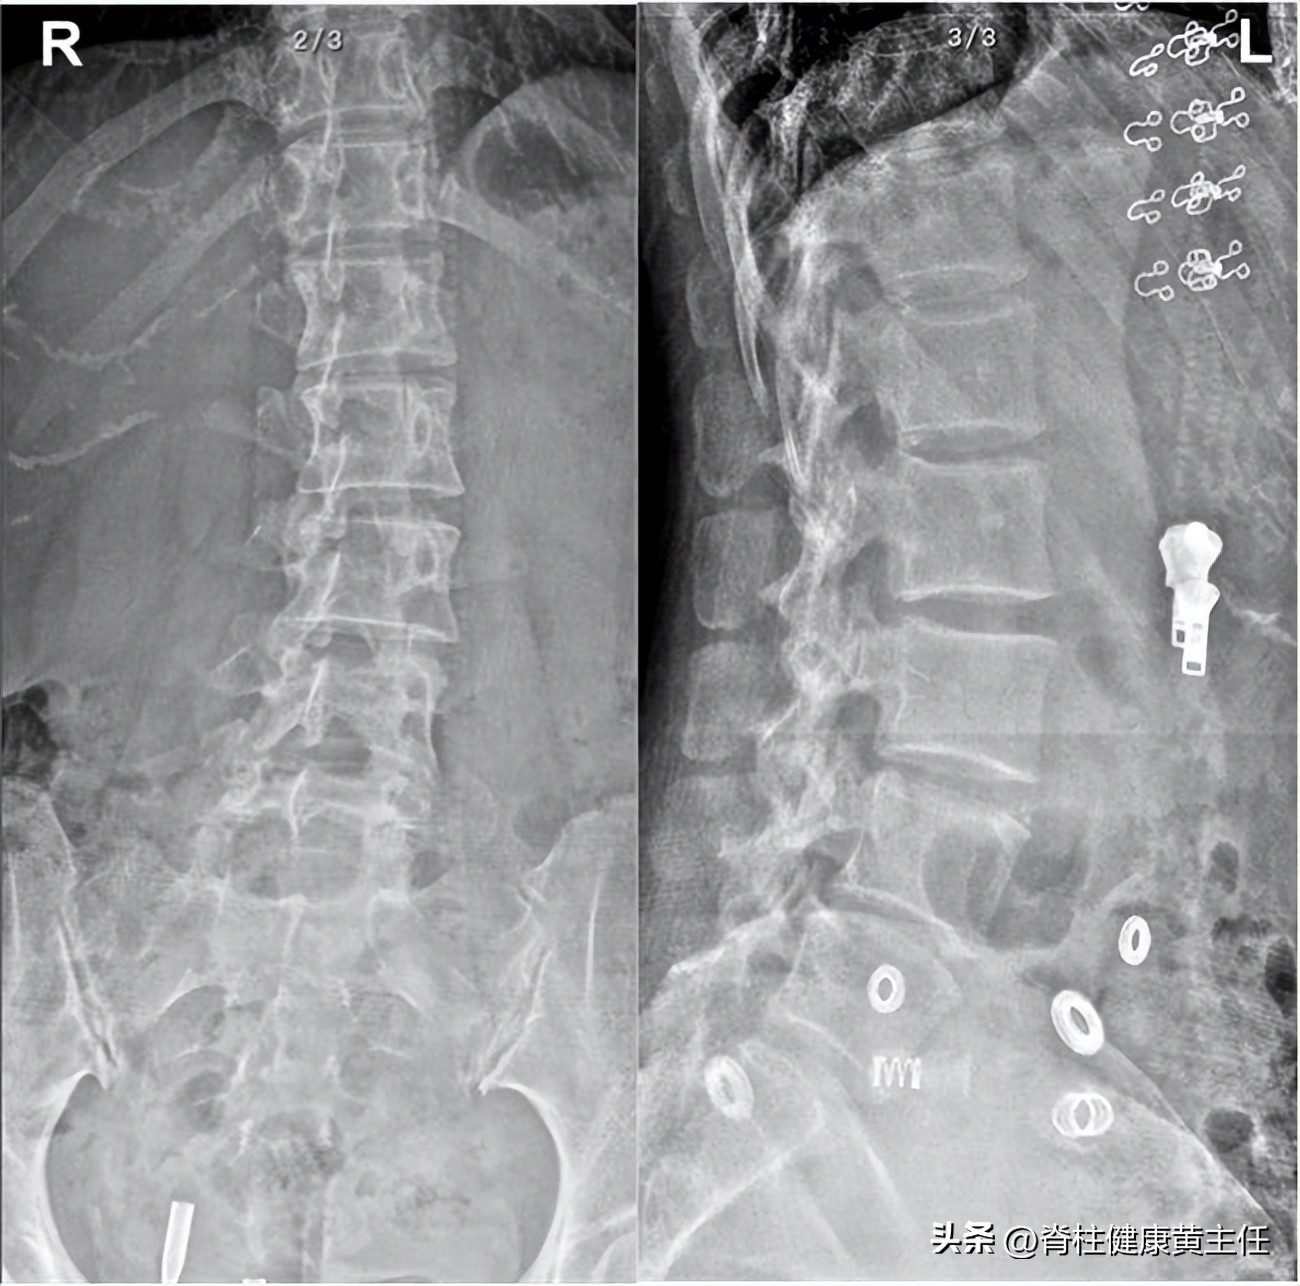

2、X光片检查:腰椎骨盆X光检查示,腰椎多棘突向右偏歪,腰椎生理曲度存在,髂骨右高左低,髂骨右髋左窄。

腰椎X光检查